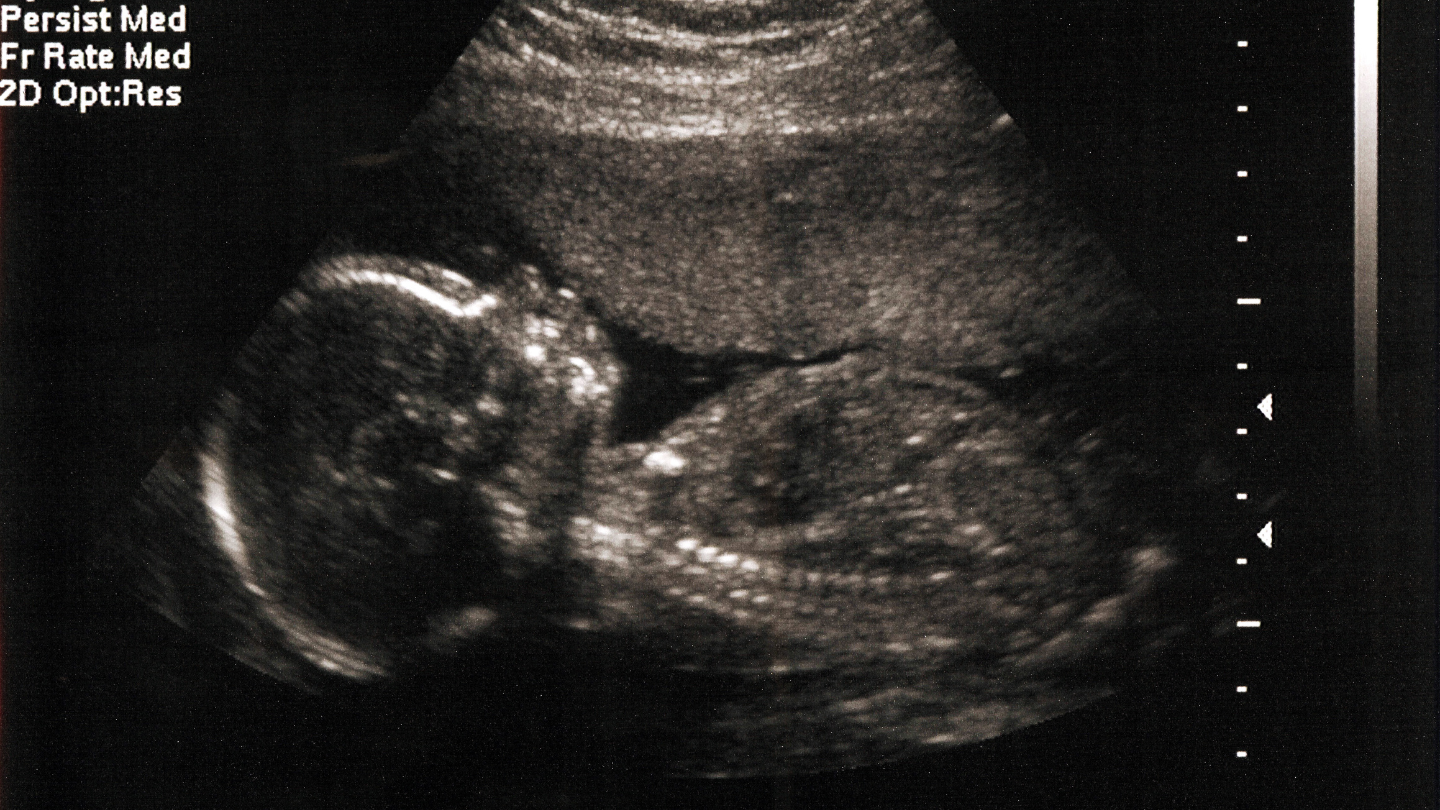

Việc siêu âm cho kết quả thai nặng khoảng 2kg có thể khiến mẹ băn khoăn liệu bé có đang chậm phát triển hay không, có cần can thiệp gì hay chỉ cần theo dõi thêm. Bài viết dưới đây của Tiêm chủng Long Châu sẽ giúp mẹ hiểu rõ vấn đề thai 35 tuần nặng 2kg có nhẹ cân không, nguyên nhân có thể gặp phải, cách xử trí an toàn và những câu hỏi thường gặp liên quan đến dấu hiệu thai nhi khỏe mạnh 3 tháng cuối.

Theo các bảng tham chiếu tăng trưởng thai nhi của Tổ chức Y tế Thế giới (WHO), cân nặng trung bình của thai nhi ở tuần 35 thường dao động từ khoảng 2,2kg đến 2,7kg (percentile 10 - 90). Vì vậy, thai 35 tuần nặng 2kg là thấp hơn mức trung bình, có thể được xếp vào nhóm nhẹ cân so với tuổi thai (small for gestational age - SGA) nếu nằm dưới percentile 10. Tuy nhiên, chưa thể kết luận ngay là nguy hiểm hay suy dinh dưỡng thai nhi chỉ dựa vào một con số này.

Cân nặng siêu âm chỉ là ước tính, thường có sai số khoảng ±15% do máy móc, tư thế thai nhi và kinh nghiệm người thực hiện. Bác sĩ sẽ đánh giá tổng thể qua các chỉ số khác qua các lần khám trước đó như:

Tóm lại, thai 35 tuần nặng khoảng 2 kg được xếp vào nhóm nhẹ cân so với mức trung bình, nhưng nếu các chỉ số khác bình thường và thai tăng cân đều đặn, mẹ chỉ cần theo dõi thêm mà không quá lo lắng.